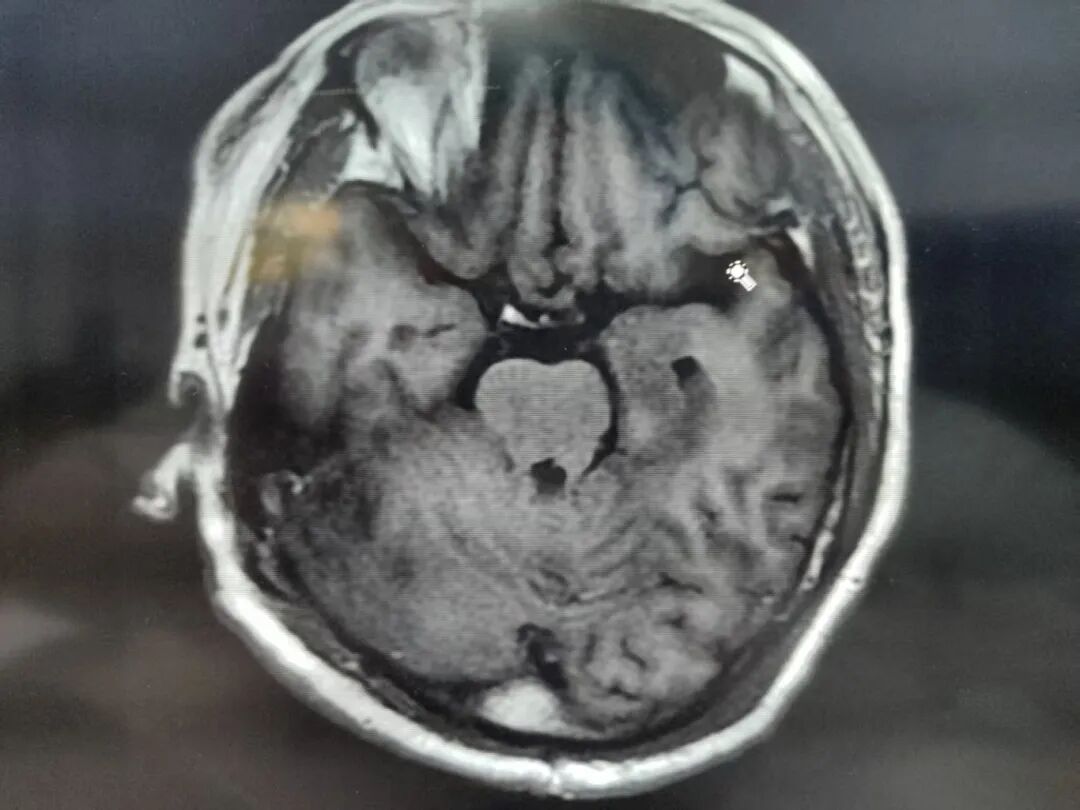

术后,患者被送往ICU继续观察,次日安返病房。病检结果显示为脑膜瘤。在医护人员的精心治疗与护理下,患者恢复良好,未发生并发症,已顺利康复出院。

(▲术后复查)